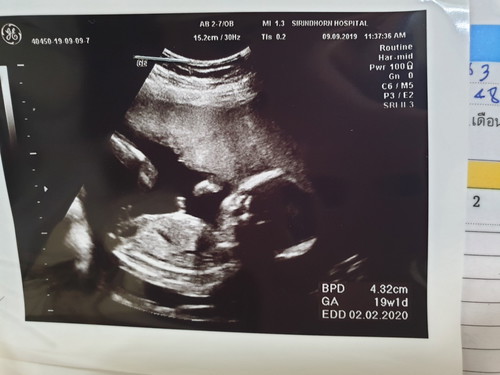

ตอนนี้เรากลายเป็นคุณแม่เลี้ยงเดี่ยวอย่างเต็มตัวแล้วคะ เนื่องจากแฟนเรา เขาไม่สนใจใยดีบอกให้มาตรวจเลือดให้เขาก็ไม่มาผลัดวันประกันพรุ่งตลอด เราขอเงินเพื่อที่จะมาซื้อนมกินบำรุงลูกเขาก็ไม่โอนมาสักที บอกจะโอนก็ไม่โอนผลัดมาเรื่อยๆ ตั้งแต่ท้องมาไม่เคยได้เงินกับมันสักบาท ตอนนี้ท้องได้19w มันไม่เคยมาหาไม่เคยมาดูดำดูดีอะไรเลย เราคบกับมัน1ปีก่อนหน้าจะตั้งท้องคุยกันแล้วว่าอยากได้ลูกด้วยกัน ถ้ามีลูกแล้วมันจะมาแต่ง เห้อไม่น่าหลงเชื่อ ผู้ชายห่วยๆแบบมันเลย ตอนท้องอ่อนๆเครียดมากทะเลาะกันทางโทรศัพท์ทุกวัน ร้องไห้แทบทุกวัน หลังๆมาเริ่มทำใจแล้วว่ายังไงก็คงไปกันไม่รอด เลยถอดใจแล้วยุติการคุยการติดต่อทุกประการ ดีหน่อยว่าที่บ้านเข้าใจให้กำลังใจตลอด แม่จะพูดเสมอว่า" อย่าคิดสั้นนะ"แม่กลัวเราคิดสั้นเพราะเราเครียดมาก กำลังใจจากครอบครัวคนรอบข้างดีมาก ซึ่งไม่เคยได้รับจากมันเลย และวันนี้หมอนัดอัลต้าซาวด์ ตัวเราและครอบครัวอยากได้เด็กผู้หญิงแต่ได้จู๋มาเลยจ้า ผิดหวังนิดหน่อยแต่ก็โอเคคะยังไงก็ลูกเรา เราจะรักและดูแลเขาให้ดีที่สุด ตอนอยู่ในห้องกับหมอ ถามหมอว่าพี่คะเราสามารถเอาชื่อพ่อออกได้มั้ยคะ? หมอกับพยาบาลตกใจถามว่าทำไมละ เราตอบว่าพ่อมันไม่ติดต่อมาคะ(น้ำตาไหลพราก สงสารตัวเอง) หมอคุยกับพยาบาลว่าได้มั้ยอ่ะ ตอนแจ้งเกิดไม่ต้องแจ้งชื่อบิดาได้นะ แล้วหมอก็ถามว่าไม่ได้อยู่ด้วยกันหรือแต่งงานกันหรอ บลาๆๆๆ เราร้องไห้แบบไม่อายหมอกับพยาบาลเลยคะ มันบีบหัวใจสุดๆ?สงสารลูก สงสารตัวเอง โทรไปขอเงินเขา เขาก็ไม่ให้สักที จนรู้สึกว่าสมเพสตัวเองมาก ทำไมชีวิตกูดูไร้ค่าอะไรขนาดนี้ มันไม่ให้ มันไม่รัก ก็เลิกไปจบ ๆไป ต่อจากนี้ไปก็จะไม่เอาตัวเองและลูกไปวุ่นวายและจะไม่ให้มันเห้นหน้าลูก หมดเวรหมดกรรมต่อกันสักที *ลูกคือทุกอย่างที่ทำให้เราอยากมีชีวิตต่อเพื่อเขา